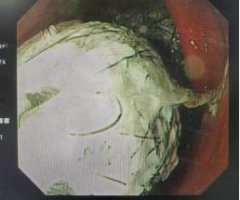

异食癖 异物 营养科 2024/09/11